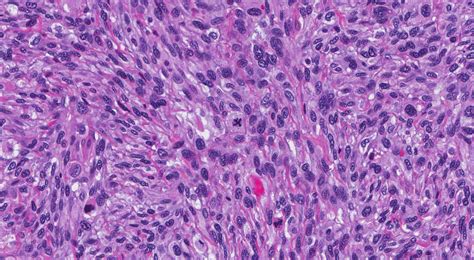

Once a doctor suspects a sarcoma, they will utilize a combination of diagnostic tools to confirm the diagnosis and determine the extent of the disease. The journey to a diagnosis usually involves imaging tests, such as X-rays, MRIs, or PET scans, which help identify the exact location and size of the tumor. A biopsy—where a small sample of the tissue is removed and examined under a microscope—is the gold standard for confirming exactly what is a sarcoma in a specific patient.

• The grade of the tumor (how aggressive the cells look under a microscope).

Sarcoma is not a single disease; it is an umbrella term for over 70 different subtypes. The way a sarcoma is categorized depends largely on the type of cell from which it originated. Understanding the subtype is critical because it dictates the treatment plan and the expected prognosis.